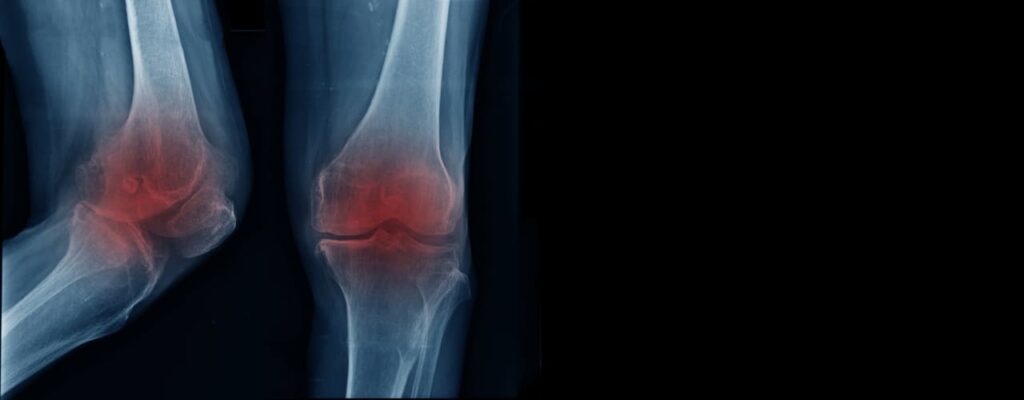

When Wear-and-Tear Slows You Down: Osteoarthritis

Osteoarthritis is the most common type of arthritis in adults. It occurs when the cartilage cushioning the joints wears down over time, often affecting the knees, hips, or hands.